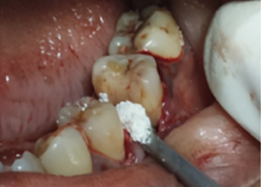

Hemisectomy

Bone Graft Placement